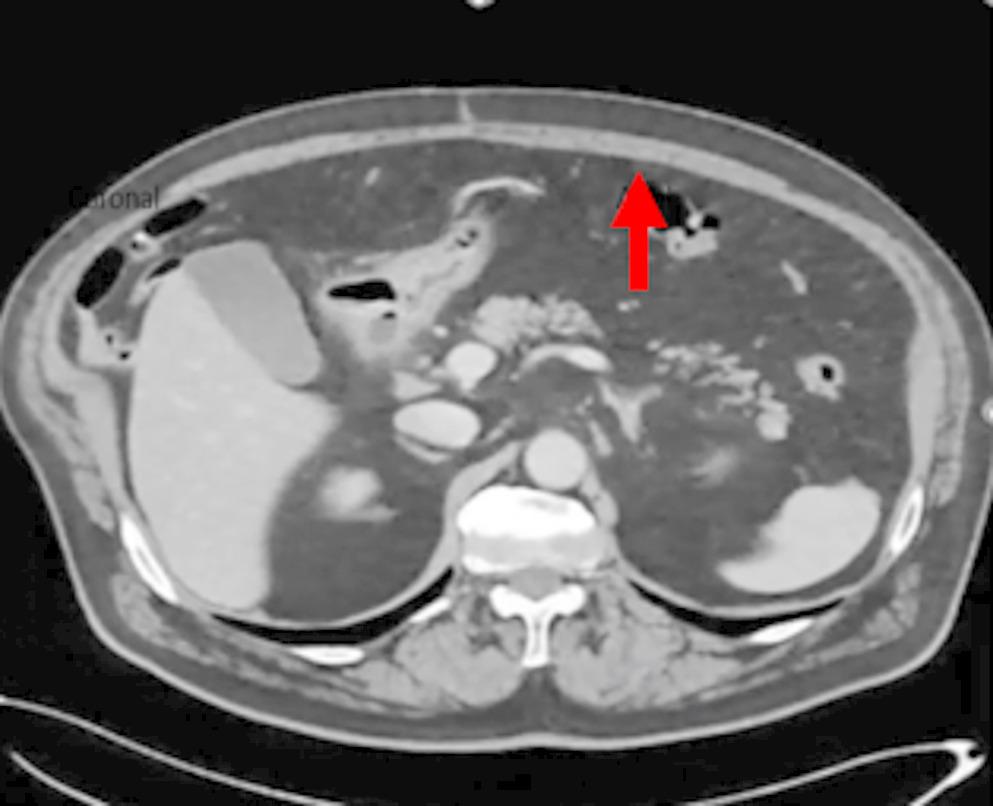

All participating radiologists were subspecialty-trained in body CT with extensive experience in postoperative CT interpretation, including a minimum of five VHR-related studies weekly. Each radiologist independently assessed 18 CT scans performed two years post-VHR. The 2- year post-operative timepoint was selected based on several considerations: (1) complete mesh incorporation and tissue remodeling typically occurs by 12–24 months, providing stable imaging characteristics; (2) this timeframe represents when many patients present with recurrent hernias requiring reoperation; and (3) it minimizes acute post-operative changes that could confound mesh visualization while maintaining clinical relevance for surgical planning. Radiologists completed a structured questionnaire to specify mesh location and type. The VHR planes were classified according to the European Hernia Society’s International Classification of Abdominal Wall Planes (ICAP) (Parker SG, et al. International classification of abdominal wall planes (ICAP) to describe mesh insertion for ventral hernia repair. Br J Surg. 2020;107(3):209–217). The planes assessed included: (1) retrorectus plane - mesh positioned posterior to the rectus muscle and anterior to the posterior rectus sheath; (2) retromuscular plane - accessed only after transversus abdominis release (TAR), with mesh extending laterally beyond the semilunar line; (3) preperitoneal plane - mesh positioned between the peritoneum and transversalis fascia; and (4) intraperitoneal plane - mesh placed within the peritoneal cavity (Fig. 1). All meshes used in this study were permanent synthetic polypropylene and categorized by density. Heavy-weight synthetic mesh (HWSM) was defined as PROLENE® Mesh, manufactured by Ethicon with a density of 95 g/m² (Fig. 2). Medium-weight synthetic mesh (MWSM) referred to Bard™ Soft Mesh, with a density of 43 g/m², and light-weight synthetic mesh (LWSM) corresponded to Ultrapro™ advanced, with a weight of 26 g/m² (Figs. 3 and 4) Detailed characteristics for all 18 cases, including mesh specifications and CT parameters, are provided in Supplementary Table 1. Additionally, the study incorporated CT scans from two control groups: a negative control group with patients who had never undergone abdominal surgery, and a positive control group with patients who had undergone laparotomy without VHR. Control CT scans were obtained at variable timepoints: positive control scans (laparotomy without VHR) were acquired 3–6 months postoperatively to capture healed surgical changes without mesh, while negative control scans (no prior abdominal surgery) had no timing restrictions as they served to demonstrate normal abdominal wall anatomy. The 3–6 month timepoint for positive controls was selected to ensure complete laparotomy healing while avoiding long-term tissue remodeling that might obscure surgical plane distinction. While this creates temporal mismatch with 24-month VHR scans, the primary diagnostic task focuses on mesh presence/absence rather than temporal evolution of surgical changes. This timepoint captures healed surgical changes without mesh-related artifacts, providing appropriate control for radiologist assessment. All radiologists were informed of the inclusion of these control scans in the study.

Fig. 2

Heavy-Weight Mesh

Bild vergrößern